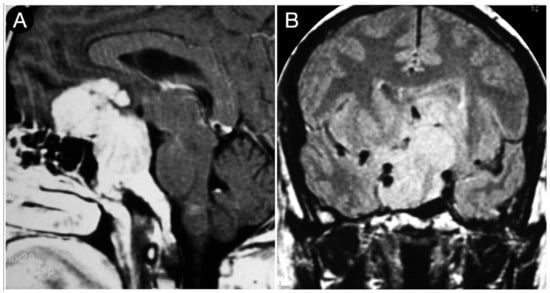

Case #1: Infradiaphragmantic Tumor with Middle Fossa Involvement through the Cavernous Sinus

3.4. Retrosellar Extension